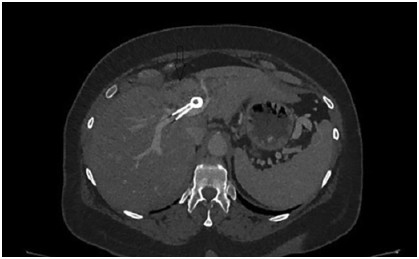

Abstract: Hilar cholangiocellular carcinoma (CCC) is a malignant neoplasm of epithelial origin occurring at the confluence of the right and left hepatic bile ducts. Typically, these tumors are small, poorly differentiated, exhibit aggressive biologic behavior with non-specific symptoms and tend to obstruct the intrahepatic bile ducts. Surgery is the only available curative option. Unfortunately, in less than half of the patients a complete resection is possible with poor survival rate in unresectable cases. In this report, we present the case of a 58-year-old woman with a history of unresectable hilar cholangiocarcinoma. Initially she was treated with intraductal dilatation of malignancy and placement of a plastic stent and chemotherapy (Gemcitabin® and Platinol®). Two years later she underwent a second-line chemotherapy with Gemcitabin® and Oxyplatin® because of tumor progression. Despite a second line chemotherapy and placement of an uncovered self-expandible metal stent (ucSEMS) that was extended later on by stent-in stent technique, there was tumor progression which led to a complex course with relapsing obstructive cholangiosepsis and cholestasis. Because of tumor ingrowth, endobiliary radiofrequency ablation of the malignant stenosis was performed in repeated sessions. This case illustrates that radiofrequency ablation of solitary malignant biliary obstruction is feasible, safe and allows an improvement of quality of life in non-operable patients.